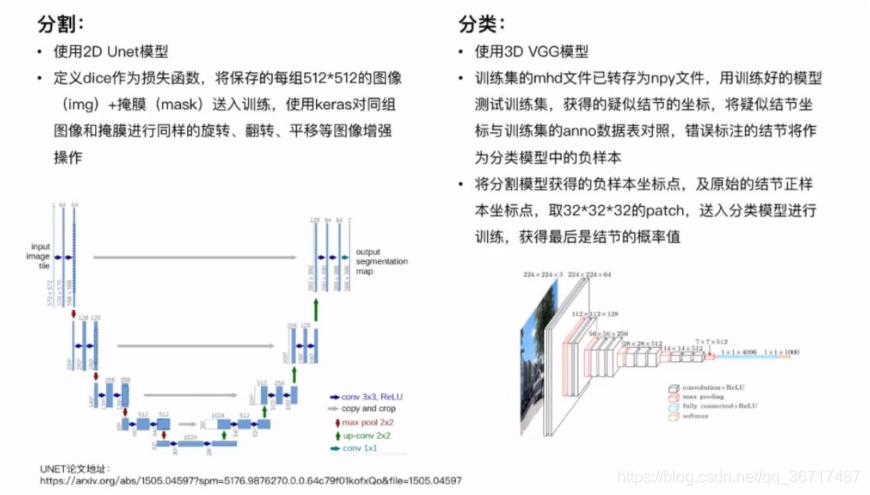

2.Unet网络介绍

Unet是一个在医学图像处理领域,应用很广泛的网络结构,是一种全卷积神经网络,输入和输出都是图像,没有全连接层。较浅的高分辨率层用来解决像素定位的问题,较深的层用来解决像素分类的问题。U-NET 构造了一个收缩网络和一个扩张网络,形成了一个 U 型结构。收缩过程通过不断的卷积(convolution)和池化(pooling)操作提取图片特征。扩张过程与收缩过程相对应,通过上采样(upsampling)和卷积操作来获取图片的特征。U-NET 的特点在于收缩网络和扩张网络是相互映射的关系,在扩张的过程中,通过合并与之映射的收缩层特征补全丢失的边界信息,提升预测边缘信息的准确性。与SegNet,VGG 等网络结构相比,U-NET 具有训练时间短,结构简单,样本需求少等优势。

5.分类网络

分割网络检测的疑似结点中含有大量的假阳性,比例大约是1:20,因此需要一个分类网络进行假阳性衰减,判别每一个疑似结点是否是真阳性,并给出属于真阳性的概率。

数据处理步骤

分割网络检测处的疑似结点作为分类网络的输入数据,进行与分割阶段相同的归一化,翻转以及随机平移。由于正负样本比例悬殊,在训练分类网络的时候,控制正负样本比例为1:3,比1:1或者不控制比例训的准确率更高。